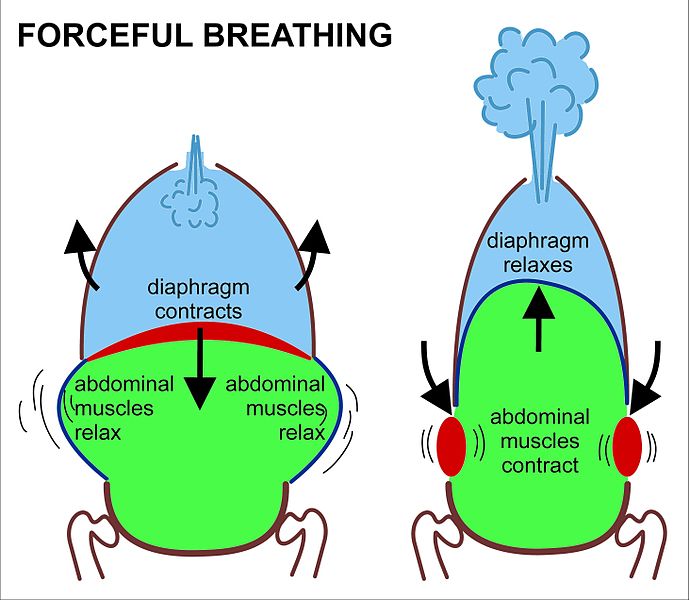

eupnea – also known as quiet breathing or the resting respiration is the normal breath. Here the process is completely passive and engages the elastic recoil of the lungs. In comparison to eupnea, apnea is the absence of respiration, dyspnea is diffcult respiration, bradypnea is slower respiration, and trachypnea is fast respiration.

Emphysema – With age there are various structural, functional and immunological changes that take place within the respiratory system. The anatomical changes include thoracic spine and chest wall distortion leading to impairment in the respiratory system and heavier breathing load. Due to the loss of its supporting structures, the lung parenchyma faces “senile emphysema” i.e., dilation of air spaces. In addition to that, the airway clearance needed for effective cough is also hindered due to the loss of strength in the respiratory muscles.

Elastcitiy (compliance) – Aging is strongly associated with a significant decrease in elastic recoil and fibrous strength. With age, there is inevitable reduction in the thoracic compliance and augmentation in lung compliance. Thoracic (chest wall) compliance regulates the elastic load during inhalation whereas the lung compliance regulates the rate and force of exhalation. With aging there are significant structural changes to the thoracic spine and cage which ultimately leads to depletion in chest wall compliance.